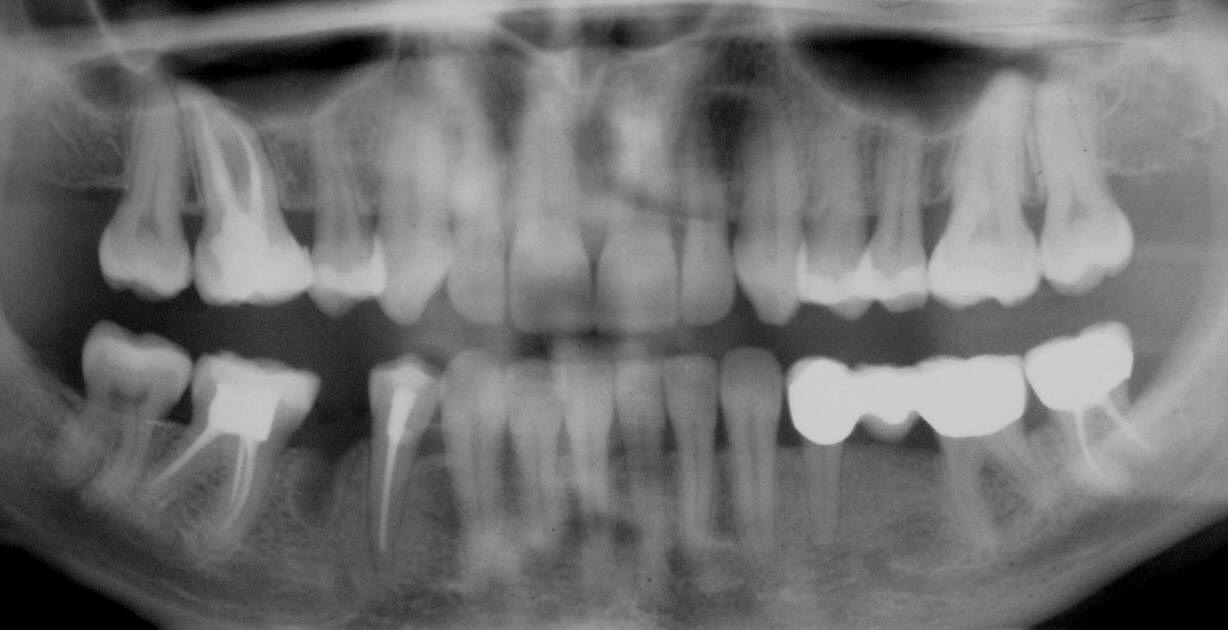

OPT anlässlich der Erstuntersuchung im November 2004: Zustand nach Ex 45, unauffälliger Wurzelbehandlung an 16, unvollständige WF mit diskreter Beherdung an 46, unauffällige WF an 44 mit deutlich verbreitertem PAR-Spalt (Klick!)